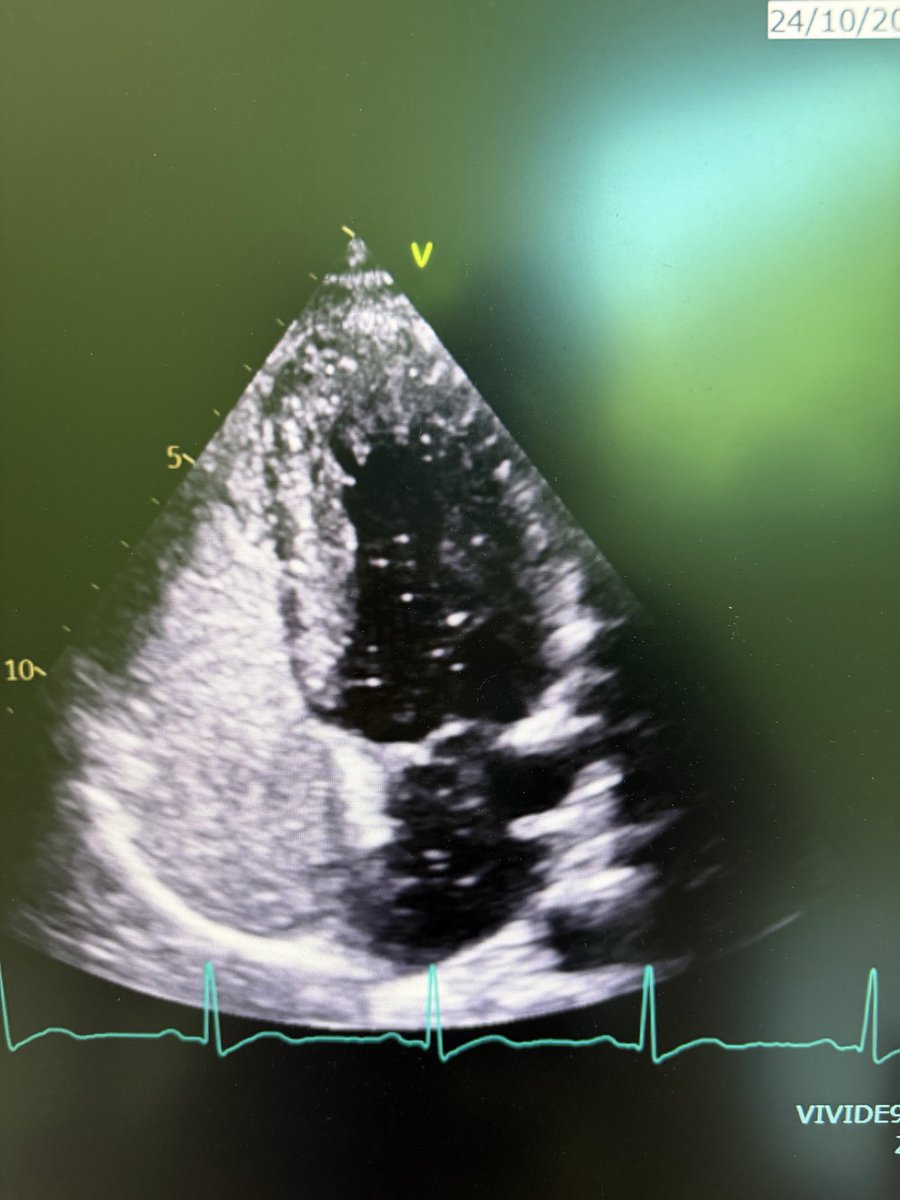

Two weeks ago, a 54-year-old patient recovering from open-heart surgery (CABG) suffered a major stroke. • Symptoms: Sudden inability to speak + right-side paralysis. • Action: Immediate Mechanical Thrombectomy to remove the brain clot.

Manish Kumar Yadav tweet mediaManish Kumar Yadav tweet mediaManish Kumar Yadav tweet mediaManish Kumar Yadav tweet media